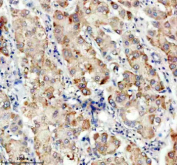

Immunohistochemical staining of TDO2 using anti-TDO2 antibody. TDO2 was detected in a paraffin-embedded section of human liver cancer tissue. Heat mediated antigen retrieval was performed in EDTA buffer (pH 8.0, epitope retrieval solution). The tissue section was blocked with 10% goat serum. The tissue section was then incubated with 2 ug/ml rabbit anti-TDO2 antibody overnight at 4oC. Peroxidase Conjugated Goat Anti-rabbit IgG was used as secondary antibody and incubated for 30 minutes at 37oC. The tissue section was developed using an HRP secondary and DAB substrate.